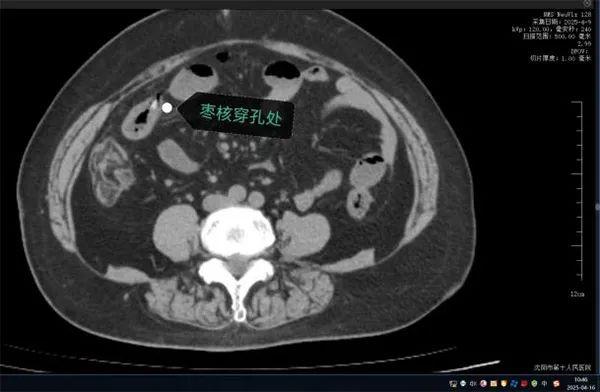

案例二 :刺穿小肠 生死一线

无独有偶,63岁的康阿姨近日因突发“刀绞般”剧烈腹痛,深夜被紧急送往沈阳市第十人民医院。短短数小时内,她出现高热、腹肌强直等弥漫性腹膜炎症状。CT检查显示腹腔游离气体,高度怀疑消化道穿孔。

家属回忆,当天上午康阿姨吃粽子时误吞两颗枣核。医生会诊判断枣核尖端已刺穿小肠,紧急手术取出异物。

图源:沈阳市第十人民医院